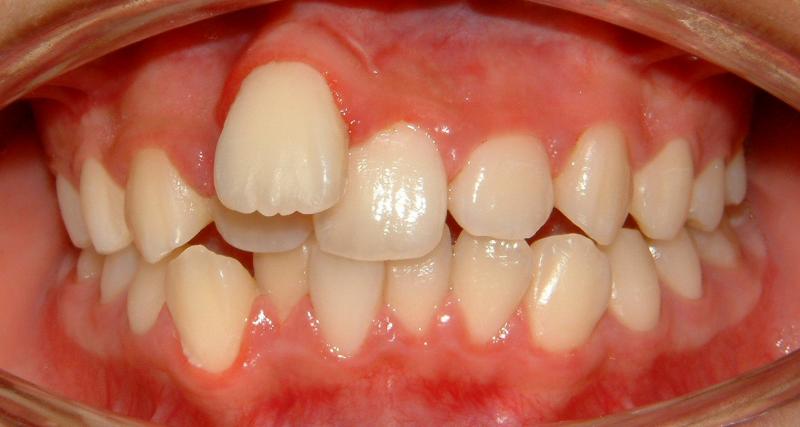

The upper right central incisor and lateral incisor form 2 rows. It would be a fatal mistake to extract either one of these two. It might be the case if the patient has no access to the correct orthodontic treatment. In this case, the 1st premolars are removed. Initial and some progress data are presented in Figs. 1-5.

Fig. 1 Upper right central and lateral incisors, forming double rows -- front view